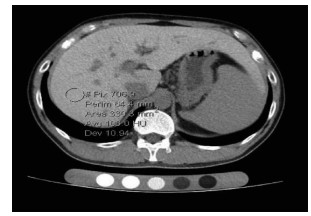

Hepatic alveolar echinococcosis misdiagnosed as intrahepatic cholangiocarcinoma: A case report

Kai ZHAO, Zhixin WANG, Shengbao WEN, Haijiu WANG, Haining FAN, Li REN

2021, 37(5): 1183-1185. DOI: 10.3969/j.issn.1001-5256.2021.05.042

Abstract(1037) HTML (359) PDF (2157KB)(63)

Abstract: